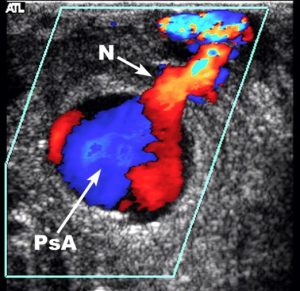

On the day post ablation Ms. X started complaining of groin tenderness. Examination revealed a preserved femoral pulse and a faint bruit that was not noted before. A groin ultrasound was ordered. The main finding is seen in the image below:

This is a pseudoaneurysm. There is a typical to and fro flow pattern in the neck. There is a typical ‘bubble’ with a ‘Yin-Yang’ flow pattern. This pseudoaneurysm measured about 1.2 cm. What would you do in this case?